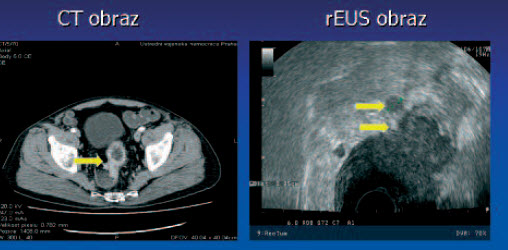

Tumor T2 N1

Tumor T3 N0